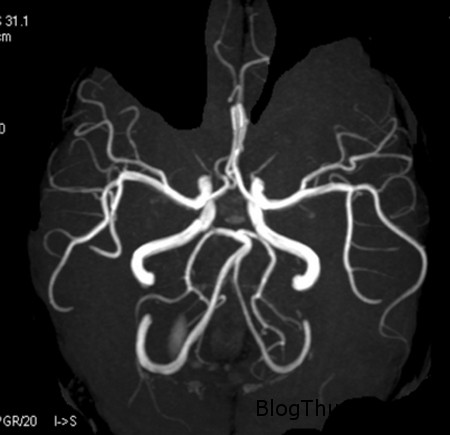

Hình ảnh chụp cộng hưởng từ.

Theo đó, căn bệnh kỳ lạ của cô gái chỉ được phát hiện ra sau khi cô tới Bệnh viện Đa khoa PLA Trung Quốc tại tỉnh Quảng Đông, Trung Quốc để thăm khám về tình trạng nôn mửa và chóng mặt. Kết quả chụp CT và MRI cho thấy, não bộ của cô bị thiếu mất tiểu não, một phần não bộ, chịu trách nhiệm điều khiển các hoạt động, vận động thể chất của cơ thể. Nằm ở vị trí sau cầu não và hành tủy, tiểu não chứa khoảng nửa nơ-ron thần kinh não bộ.